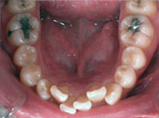

齒列擁擠的不正咬合經由擴大效果排列整齊:

Before

Proceeding

After